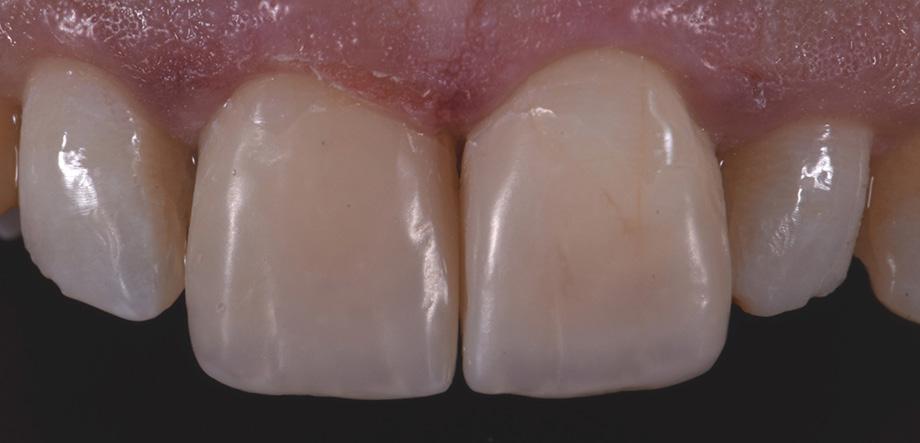

Restoring anterior teeth with large defects using composite seems to be quite challenging. With high-performance materials at hand and a systematic layering concept in mind, however, it is possible to produce highly aesthetic results in a reproducible way. The clinical case below is used to illustrate a dual-shade layering technique with CLEARFIL MAJESTY™ ES-2 Premium, a composite system with pre-defined colour combinations.

Case Example

The patient, a young male, was unhappy with the appearance of his maxillary anterior teeth. Several years ago, his central incisors had been restored with composite. These existing restorations had defective and heavily discoloured margins, while their shade did not match the adjacent natural tooth structure. The maxillary lateral incisors were peg-shaped (microdontia). Economic considerations and the desire to save as much natural tooth structure as possible made the team decide to restore all four maxillary incisors with composite. CLEARFIL MAJESTY™ ES-2 Premium became the material of choice as it eliminates the need for complicated shade combination formulas and supports predictable outcomes.

Restoring The Central Incisors

We decided to restore the central incisors first and then focus on the lateral incisors. The tooth shade was determined using the VITA™ classical A1-D4 shade guide, while composite buttons were applied to the teeth to verify the determined shade combination. In order to simplify the restoration procedure, a palatal silicon index was produced before removing the existing restorations.

Fig. 2 Intraoral image of the initial situation with defective composite restorations and microdonts. Two composite buttons on the right lateral incisor are used to verify the determined shade combination.

Fig. 3 Central incisors after removal of the old restorations and the beveling of the enamel.

Fig. 1 The patient’s initial smile.

During minimally invasive tooth preparation, bevels were created at the margins to provide for a smooth optical transition from the natural tooth structure to the composite.

An adhesive (CLEARFIL™ Universal Bond Quick) was applied after selective etching of the enamel to achieve a strong bond. With the aid of the silicon index, it was easy to create the palatal shells of the restorations with CLEARFIL MAJESTY™ ES-2 Premium in the shade A3E (enamel), which matches the determined tooth shade A3. The dentin core was built up with the same composite in the recommended shade A3D (dentin), mamelons were modelled and some CLEARFIL MAJESTY™ ES-2 Premium in the shade WD added for the incisal halo, while some individual effects (like enamel cracks) were imitated with brown stain. The build-up was finalized in the interproximal and labial areas with composite in the shade A3E. Between the central incisors, a wedge was used to retract the papilla and facilitate the designing of the interproximal contact area. The finished and pre-polished restorations already had a natural appearance.